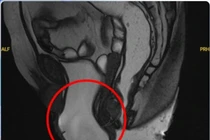

Khối sa sàn chậu đã được xử lý triệt để, không còn gây cản trở trong sinh hoạt, đồng thời tình trạng rối loạn tiểu tiện cải thiện rõ rệt so với trước mổ.

Cách đây 3 năm, bà N.T.T. (61 tuổi, ngụ tại Tây Ninh) đi khám và tình cờ phát hiện có một khối sa sàn chậu ở vùng cửa mình. Nhưng do tâm lý e ngại, mặc cảm nên bà không điều trị. Nhiều năm trôi qua, khối sa ngày càng lộ rõ, đặc biệt mỗi khi bà đi lại nhiều, hoặc ho mạnh, khối sa lại tụt ra ngoài, khiến bà gặp nhiều bất tiện trong sinh hoạt thường ngày. Bà không dám đi đâu hay làm việc nặng.